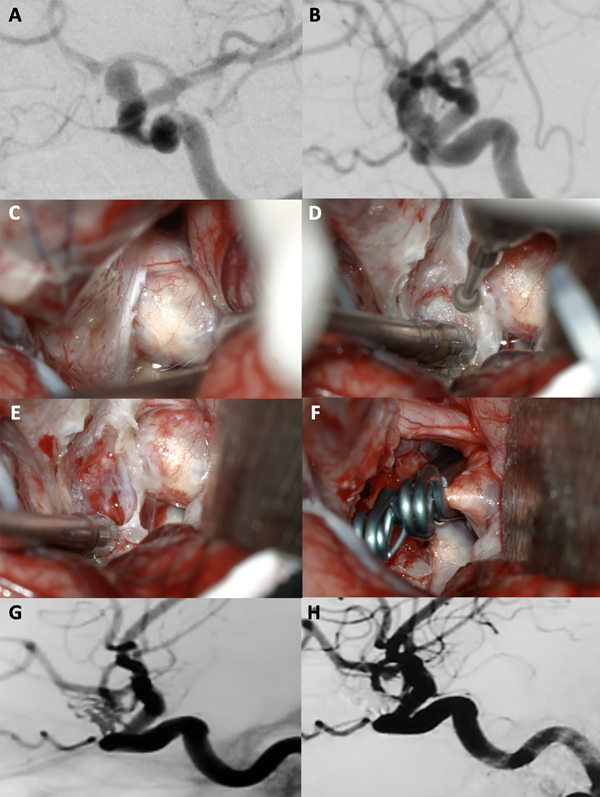

Figura 6. A-B: Se aprecia una arteriografía cerebral en vista AP y lateral que evidencia un aneurisma carótido oftálmico derecho gigante. C-F: Fotografías intraoperatorias. Observamos la cisterna óptico-carotidea; es notorio el gran efecto de masa del saco aneurismático sobre el nervio óptico. Posteriormente se realizó una clinoidectomía anterior total y sección del anillo dural distal logrando una adecuada exposición del cuello del aneurisma. Se muestra la exclusión del aneurisma con una técnica de reconstrucción vascular con múltiples clips. G-H: Imágenes de angio tomografía post operatoria que evidencia la exclusión completa del aneurisma, sin complicaciones asociadas.

Figura 7. A-B: Se aprecia una arteriografía cerebral que evidencia un aneurisma carótido oftálmico izquierdo gigante. Es notoria la presencia de una ampolla (“bleb”) de gran tamaño. C-F: Fotografías intraoperatorias. Observamos la cisterna óptico-carotidea donde es visible el saco aneurismático. Dado el tamaño de la lesión se realiza una clinoidectomía anterior total y sección del anillo dural distal logrando una adecuada exposición del cuello del aneurisma. Se muestra la exclusión del aneurisma con múltiples clips. G-H: Imágenes de arteriografía cerebral post operatoria que evidencia la exclusión completa del aneurisma con preservación de la arteria oftálmica.